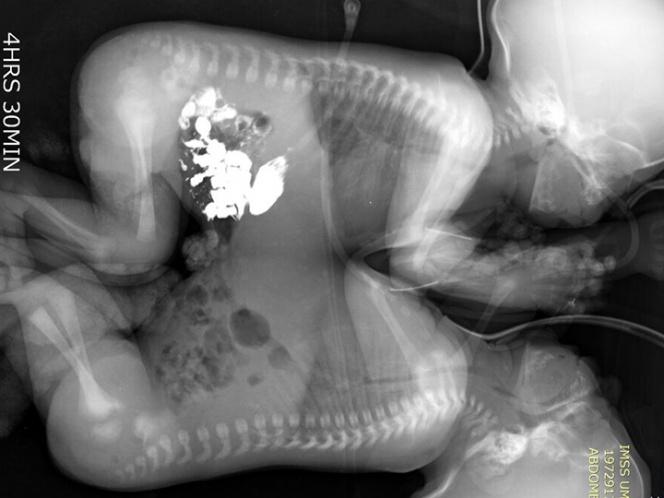

El IMSS informó que, tras diversos exámenes de tomografía, ecocardiograma y resonancia magnética, cuando los niños cumplieron 41 días de vida, fueron programados para la cirugía que los separaría.